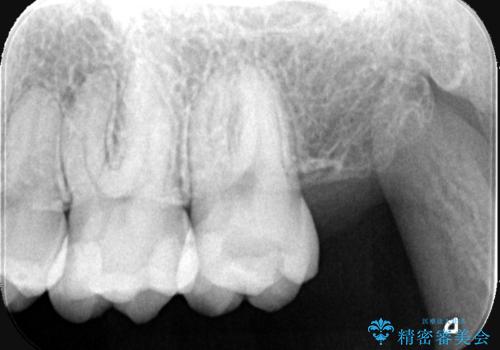

- 虫歯の治療を希望されました。一番奥の歯は虫歯が深かったことから神経を部分的に残す治療法(生活歯髄療法)や神経の治療(根管治療)についても説明し、治療介入をしました。

材料の特性を説明し、材質はどちらもセラミック、手前の歯は部分的な詰め物、奥の歯は被せ物での修復となりました。

左上7番は治療前の神経の検査では正常の範囲内の値を示しました。虫歯を削っていったところ神経まで到達したため、神経を部分的に残す治療法を選択しました。その後痛み等症状が出ず、また、神経の反応も正常であったため、被せ物にしています。